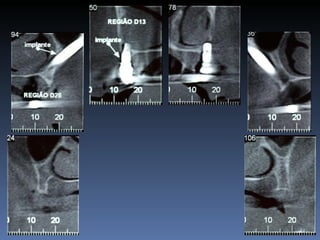

José Luis Bergamim

Idade – 53 anos

Sexo – Masculino

Raça – Caucasiana

ASA – II

Data- 25-04-2012

Diagnóstico:Desdentado parcial maxila

zona 2.2, defeito horizontal

Plano de tratamento: Reabilitação com 1 bloco “onlay”

autógeno proveniente do Ramo de Mandíbula; para

reabilitação futura com implante endo-ósseo.

Espessura Residual

2,5 mm

Defeito Horizontal

Espessura após reabilitação

8,8 mm